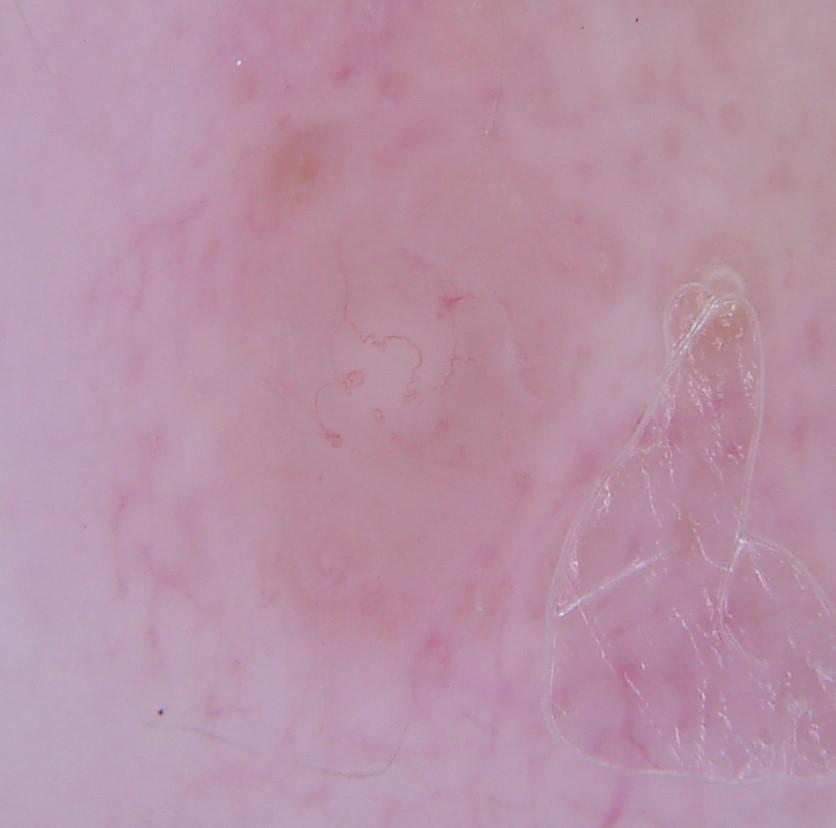

{

"age_approx": 65,

"anatom_site_general": "lower extremity",

"concomitant_biopsy": true,

"dermoscopic_type": "non-contact polarized",

"diagnosis_1": "Benign",

"diagnosis_2": "Benign melanocytic proliferations",

"diagnosis_3": "Nevus",

"diagnosis_4": "Nevus, Atypical, Dysplastic, or Clark",

"diagnosis_5": "Nevus, Atypical",

"diagnosis_confirm_type": "histopathology",

"family_hx_mm": false,

"image_type": "dermoscopic",

"melanocytic": true,

"patient_id": "IP_3168027",

"personal_hx_mm": true,

"sex": "female"

}